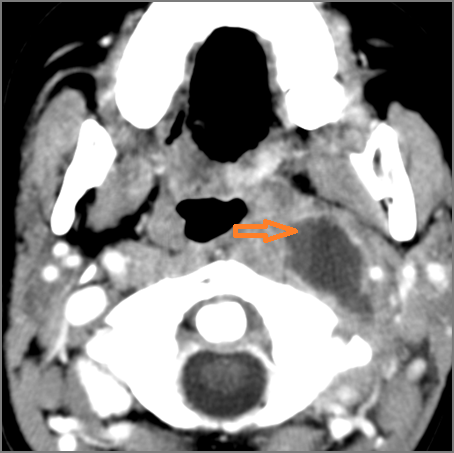

There is abscess at the periphery of the lymphoid tissue of the palatine tonsil within the potential peritonsillar space.

If there is suppurative retropharyngeal adenopathy what is the maximum short axis dimension of the largest suppurative node. MEASUREMENT

There is abscess within the adjacent deep neck, retropharyngeal and/or prevertebral spaces.

If there is suppurative cervical adenopathy the purulent material outside the lymph node(s) capsule(s).